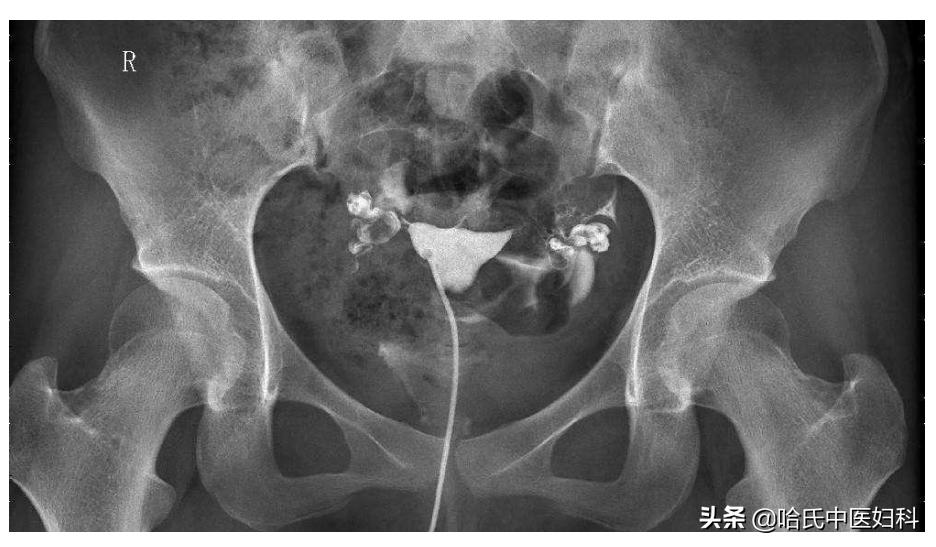

如今24岁的她已结婚嫁人,她老公也很疼她,可是结婚一年都没有孩子,老公检查没有问题,做了子宫输卵管碘油造影,结果提示双侧输卵管伞端堵塞。这下慌了,原本以为自己是易孕体质,如今被诊断为“继发性不孕”。

由于受术者有较重的宫颈炎或手术时消毒不严,可将细菌带入宫腔,从而引起输卵管炎造成输卵管阻塞,阻碍卵子和精子相遇受精。

多次人流最容易导致就是输卵管堵塞,输卵管不通一般不明显, 少数输卵管不通患者,会出现小腹一侧的疼痛、或小腹两侧疼痛、下坠感、分泌物增多、腰痛等表现,或月经来潮时血量增多等 ,只有通过做输卵管通液实验后才得知。

在这里要特别说明, 备孕女性,一般在做输卵管造影检查之前,女性卵巢功能以及监测排卵,男方进行精液常规分析。如果以上都没有问题的话,此时建议患者行输卵管造影检查。